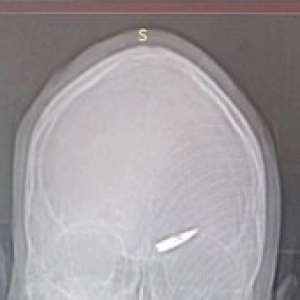

🇷🇺Морской пехотинец с позывным «Шима» целую неделю прожил с пулей, застрявшей у него в голове.

Он выполнял боевое задание на Курском направлении, когда в бою его каска была сбита, ему показалось, что пуля пролетела мимо, лишь слегка касаясь его. Несмотря на это, боец продолжил выполнять задание и получил осколочные ранения лица от взрыва вражеской гранаты. Позже его эвакуировали и доставили в госпиталь.

❗️В медицинском учреждении врачи провели рентген и были поражены увиденным. На снимках обнаружили ту самую пулю, которая попала в лоб бойца в области левой брови неделю назад, и он даже не заметил этого.